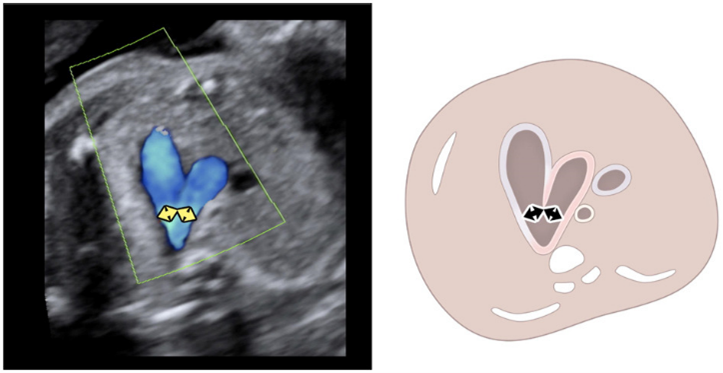

KI‑gestützter Screening‑Assistent für das fetale Herz und Gehirn

Fetoly ist die erste KI‑basierte Echtzeitlösung für den fetalen Ultraschall und unterstützt eine vollständige und standardisierte Untersuchung.

• Erkennt sofort über 100 zentrale fetale Strukturen

• Echtzeit Verhältnismessungen zur Unterstützung bei der Erkennung von Pathologien